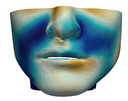

3.3. Simulation Error and Performance

4.1. Analysis of Simulation Accuracy

- Chin. Overall, the amount of error at the chin area is very low. This could be explained by the fact that the skin at the chin is very thin, and the coupling to the mandible makes the simulation highly predictive.

- Lips. In other regions, such as the lips, skin slides strongly over the underlying bones and teeth, and the deformation result is more difficult to predict. Overall, we observe higher variability in the error at the lips, and also some patients with higher error.

- Nose. The quality of the prediction of the deformation of the nose varies strongly across patients. In this case, the variability may depend on the type of surgery performed on each patient’s anterior nasal spine. This type of surgery is not easy to identify in the post-operative CBCT image due to the presence of bone grafts or fixation plates.

- Neck. Finally, we observe large error in the neck area (e.g., patients M5 and M8), and specifically at the junction point between the submental area and the neck (“C point” or “cervical point” in cephalometric analysis). This error was accounted for in our quantitative analysis, which negatively biased the overall results. However, this area is not of special interest to orthognathic surgeons. The deformation is known to be produced by a retraction of skin after surgery, but surgeons do not account for this effect during pre-operative planning.